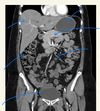

label the arrows